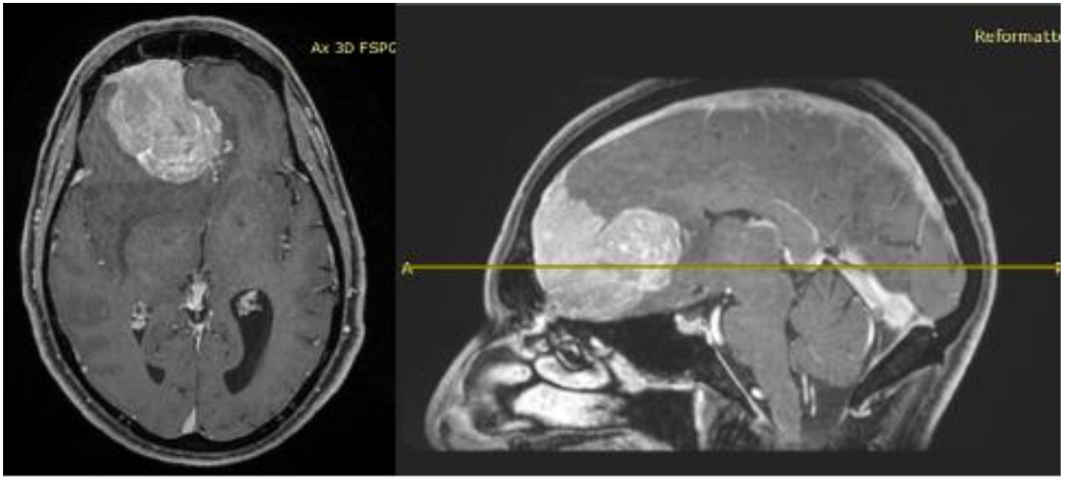

His clinical history started in 2012 with headaches, visual disturbances and behavior’s changes. MRI documented a spheno-ethmoidal lesion with a homogeneous contrast enhancement and with involvement of right anterior skull base (Figure 1). The patient underwent right subfrontal craniotomy with tumor resection. A post-operative MRI showed the apparently complete excision of lesion (Figure 2). Histopathology confirmed the radiological suspicion of meningioma (WHO I). The patient was discharged without complications.

Figure 1.

Pre-operative brain MRI showing the anterior cranial fossa meningioma with perilesional oedema.